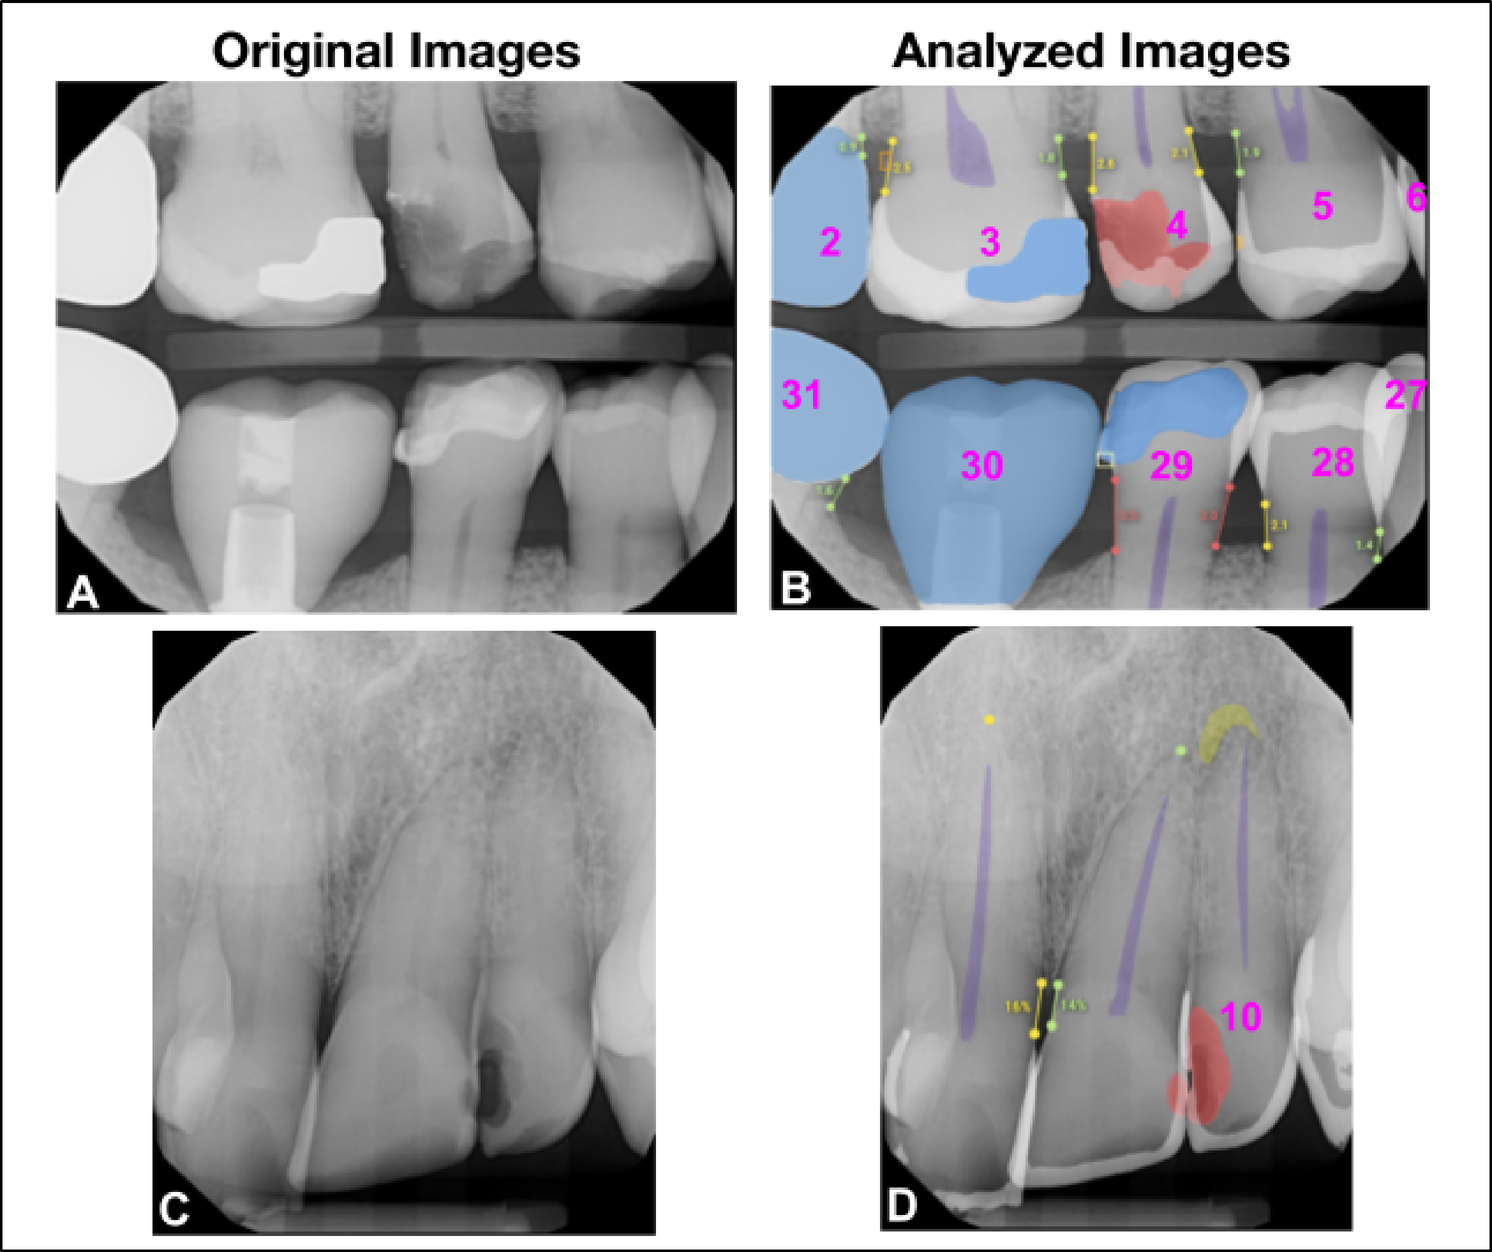

Fig. 2

This figure illustrates the clinical findings on dental radiographs as they appear in their original state and as analyzed by the Overjet AI platform. Images (A) and (C) are the original radiographs; images (B) and (D) are analyzed radiographs by the Overjet AI platform. Image B has segmentations in white to represent enamel, purple for pulp, blue for restorations including implant restorations, red for caries, marginal discrepancies in yellow box, calculus in an orange box, and millimeter bone level measurements in green, yellow and red corresponding to the value measured. Tooth numbers are presented in pink. Image (D). In addition to identifying caries and measuring bone levels, this radiograph includes a PARL, indicated as a yellow-green crescent shape at the apex area of tooth number 10.